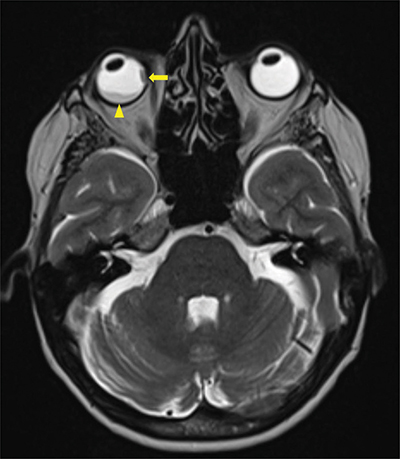

Figure 3

Axial T2 Dixon MRI-scan showing a second intra-orbital metastasis (arrow) invading all layers of the eyeball including sclera and a secondary retinal detachment (arrowhead).